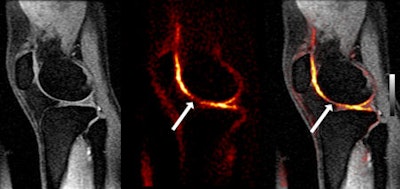

One advantage of sodium MRI is that no contrast agents are required, as Stanford researchers take advantage of sodium's high natural abundance in normal articular cartilage. "In unhealthy cartilage, sodium is depleted," Gold said. "When we look at healthy cartilage, we see a nice thin, bright area of sodium signal in the cartilage, but when we look at unhealthy cartilage we see asymmetric appearances and irregular signal intensity. This is simply a pure measure of the sodium that is there."

![]() |

| Image courtesy of Dr. Garry Gold. |

As of February 2, Stanford has scanned 17 patients with anterior cruciate ligament injuries in the past 10 years or so. The researchers are looking for differences in sodium signal between a patient's injured knee and the healthy knee "because these patients are at high risk for the progression to osteoarthritis in the knee that was injured, even if it was surgically repaired," Gold said.